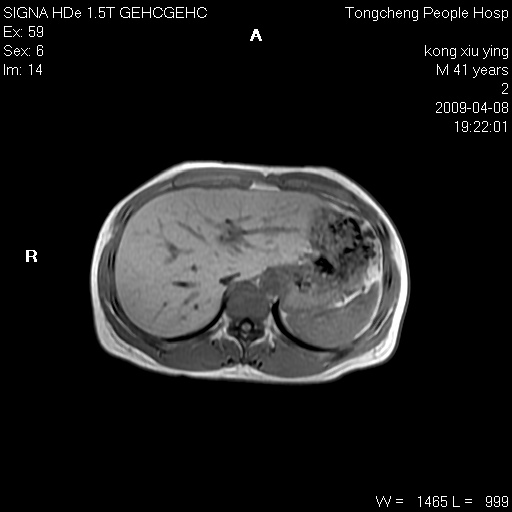

标题: CL1008:【经典】胆囊石榴籽样结石。

女,41岁。健康体检——彩超提示:胆囊显示不清。平素健康,无不适感。

腹部mr扫描及mrcp,图像如下:

标题: 胆囊阴性结石ct图片

好啊!我有ct的插进来啊,楼主请允许噶。